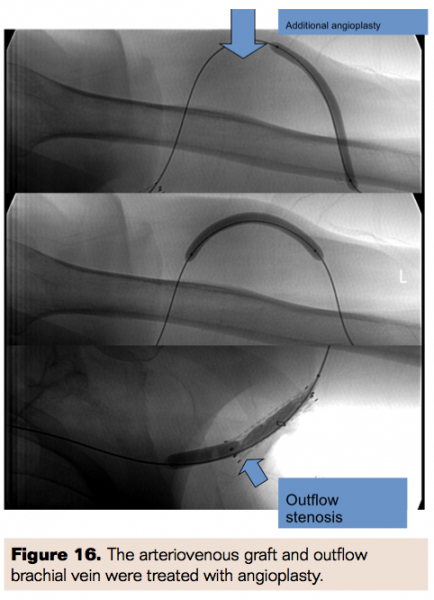

An 85-year-old male with ESRD had a brachiobasilic straight AVG previously placed. Prior intervention necessitated placement of a covered stent for outflow stenosis. He presented to the office with occlusion of his AVG access. Initial fistulogram confirmed occlusion of the AVG (Figure 15). A Glidewire was used to traverse the occluded graft and outflow vein after access was gained via a direct brachial artery puncture. Angiojet mechanical thrombectomy was then performed to reestablish access patency. Angioplasty was performed on the graft and outflow brachial vein (Figure 16). Imaging post procedure showed excellent flow through the fistula (Figure 17).